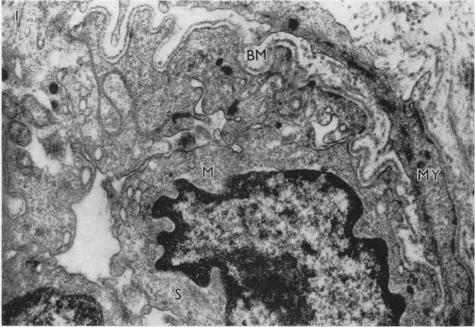

AN ELECTRON MICROSCOPE STUDY OF HUMAN BREAST CELLS IN FIBROADENOSIS AND CARCINOMA.

Br J Cancer. 1964 Dec;18(4):682-5. doi: 10.1038/bjc.1964.78.